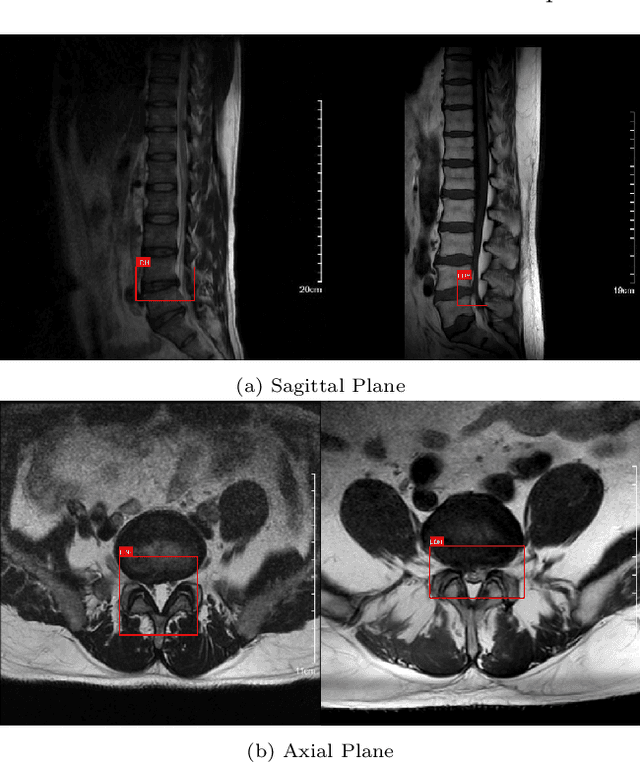

Abstract:Lumbar disc herniation (LDH) is a common musculoskeletal disease that requires magnetic resonance imaging (MRI) for effective clinical management. However, the interpretation of MRI images heavily relies on the expertise of radiologists, leading to delayed diagnosis and high costs for training physicians. Therefore, this paper proposes an innovative automated LDH classification framework. To address these key issues, the framework utilizes T1-weighted and T2-weighted MRI images from 205 people. The framework extracts clinically actionable LDH features and generates standardized diagnostic outputs by leveraging data augmentation and channel and spatial attention mechanisms. These outputs can help physicians make confident and time-effective care decisions when needed. The proposed framework achieves an area under the receiver operating characteristic curve (AUC-ROC) of 0.969 and an accuracy of 0.9486 for LDH detection. The experimental results demonstrate the performance of the proposed framework. Our framework only requires a small number of datasets for training to demonstrate high diagnostic accuracy. This is expected to be a solution to enhance the LDH detection capabilities of primary hospitals.